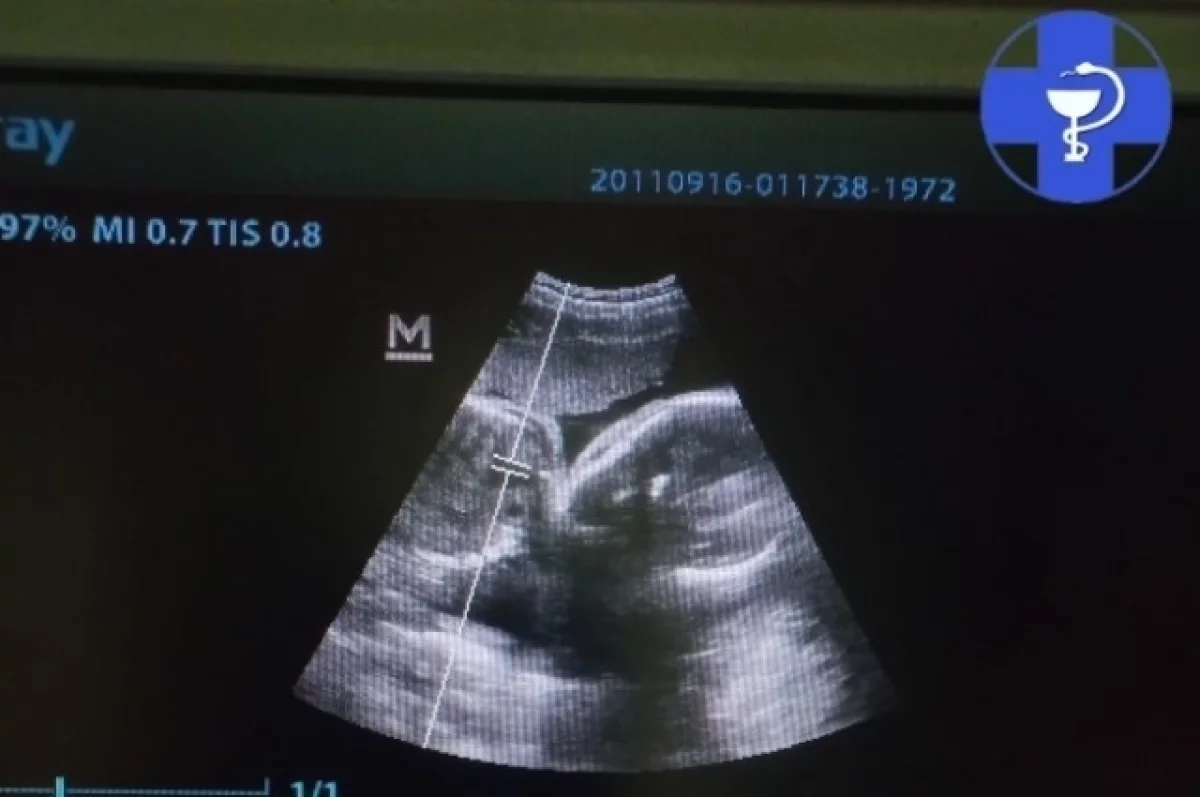

В Саратовской области собаке породы папийон потребовалось срочное хирургическое вмешательство в виде кесарева сечения из-за многоплодной беременности.

Причиной для немедленной операции послужило обнаружение брадикардии у одного из четырех щенков — частота сердечных сокращений упала до 142 ударов в минуту.